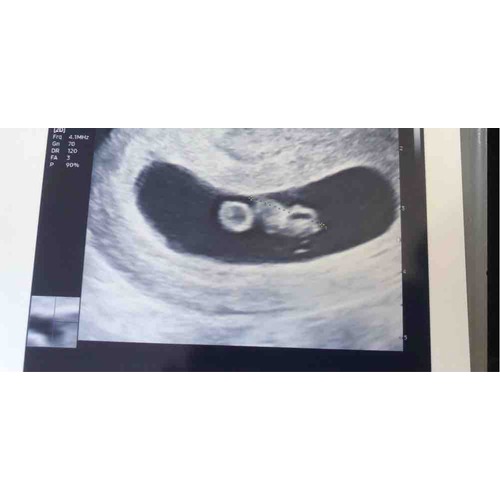

6+5w. Gisteren echo gehad ivm medische redenen!